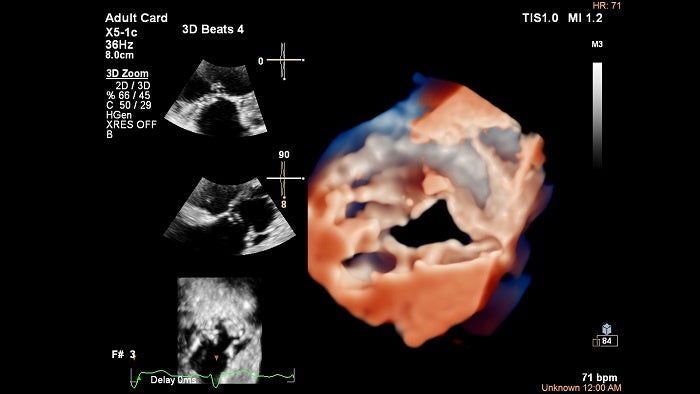

X5-1cを用いた三尖弁のTrueVueイメージ

- 「nSIGHT Plus」に基づいた画像処理Image Boostで2D画像、3D画像ともに進化しており、特に従来、体表エコーでは困難であった三尖弁や肺動脈、左室心尖部などの描出能が向上します。